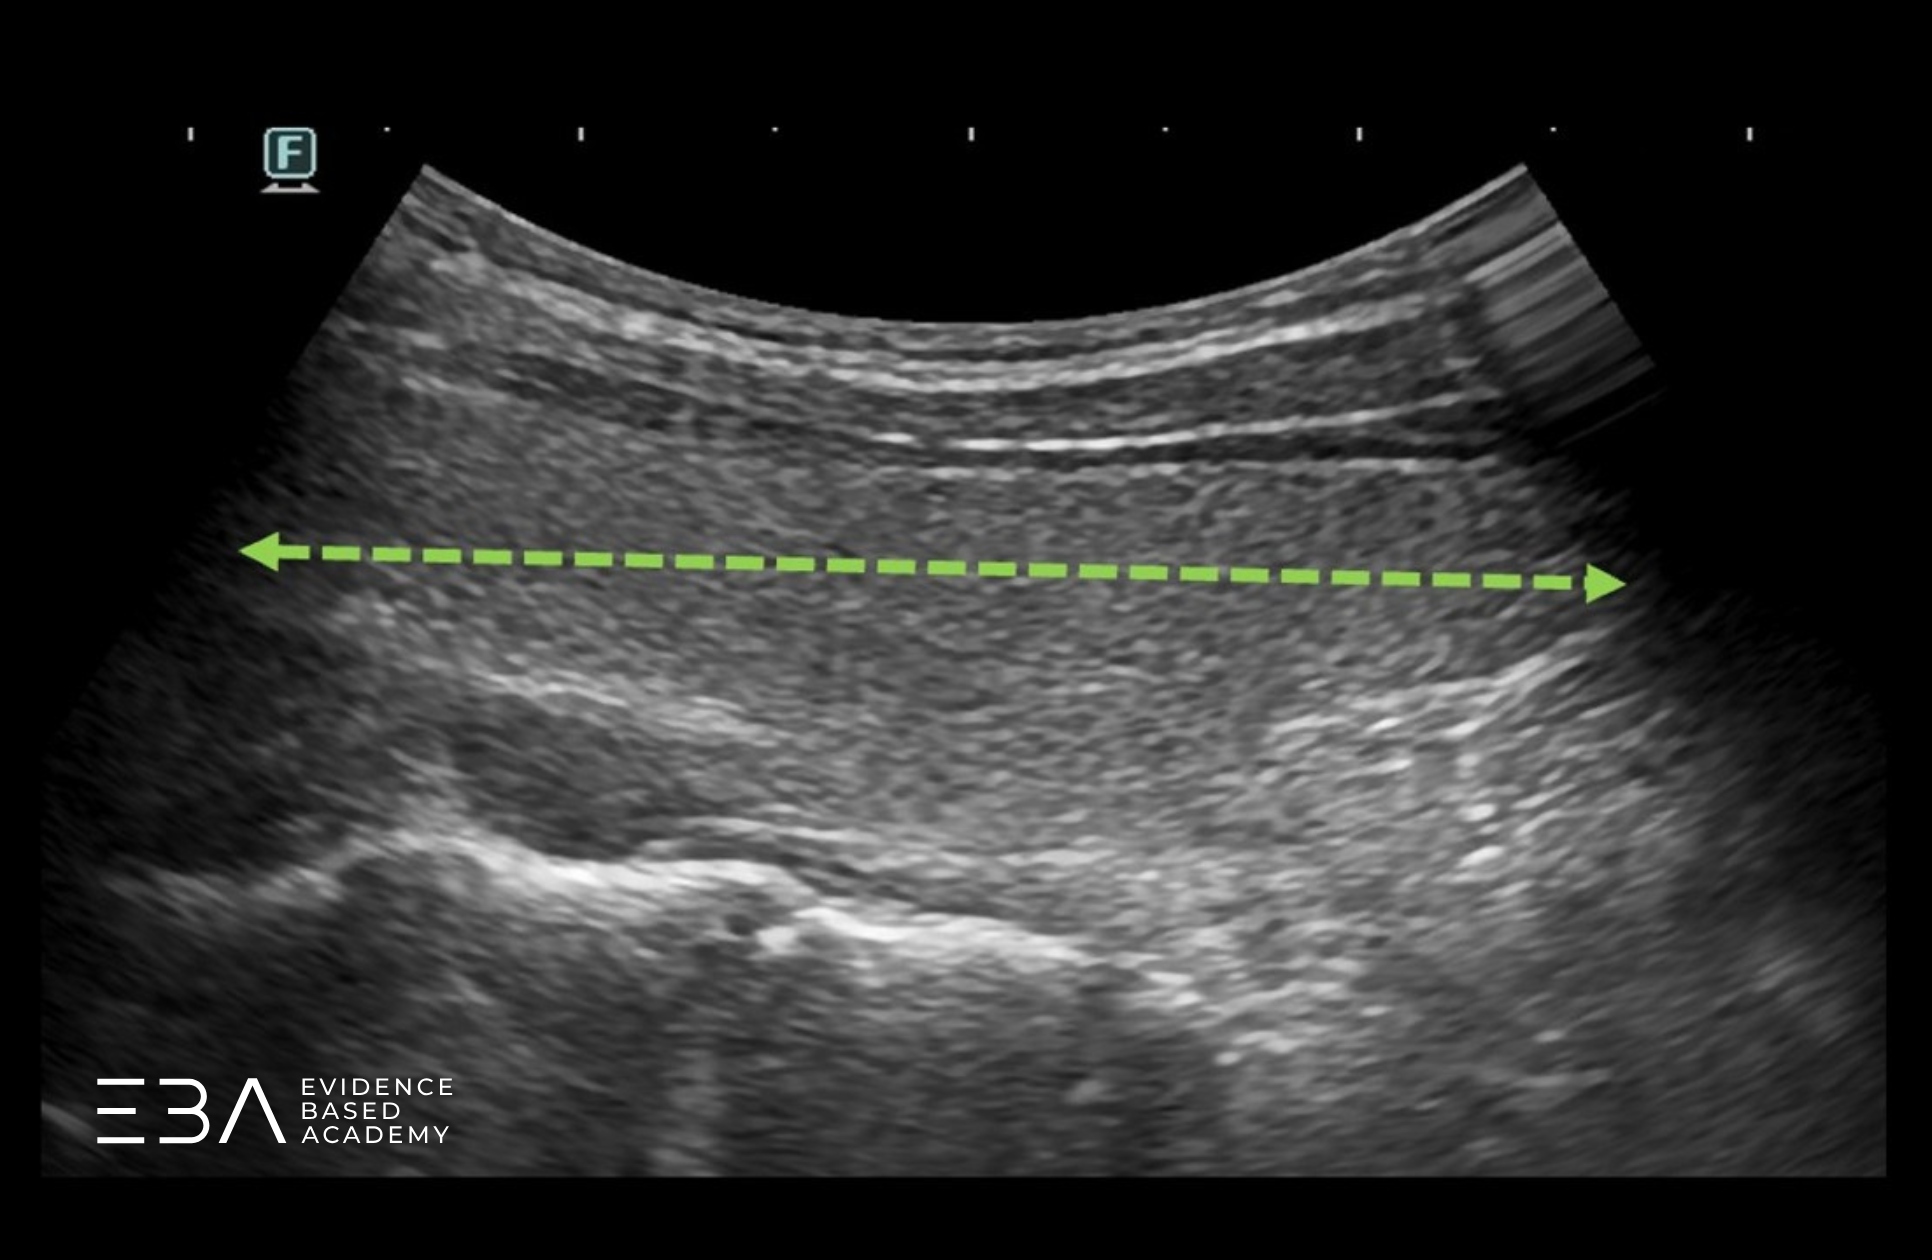

Echogeniczność miąższu tarczycy oceniamy względem echogeniczności otaczających ją mięśni (mięśni podgnykowych i MOS). Prawidłowa echogeniczność miąższu tarczycy jest wyższa od echogeniczności otaczających mięśni i jest taka sama w każdej jej części.

Echogeniczność tarczycy w porównaniu do mięśni.